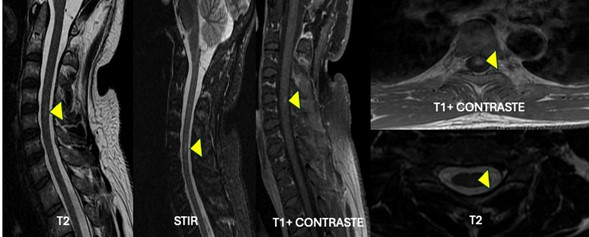

Fig. 1. Imágenes de resonancia magnética cervical, secuencias de T2, STIR y T1 con contraste. Corte sagital y axial a nivel C4-C5. Lesión en localización posterior central enfrente del disco intervertebral C4-C5, redondeada de incremento en la intensidad de la señal, de contornos mal definidos y afectación menor de 30 % del diámetro de la médula espinal en secuencias de T2, sin efecto expansivo asociado que realza de manera homogénea con el medio de contraste.